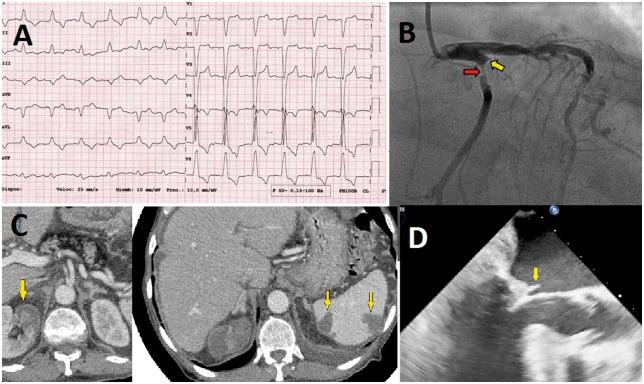

感染性心内膜炎相关心肌梗死:病例系列

Myocardial infarction associated with infective endocarditis: a case series.

CASE PRESENTATION

We report a case series of three patients with acute coronary syndrome (ACS) in IE. The first patient presented with non-ST-elevation ACS. He underwent a stent placement for late-diagnosed embolic myocardial infarction, after which he was treated conservatively without valve replacement, with good results. The second patient with ST-elevation presented with ACS, for which conventional balloon angioplasty and successful double valve replacement were performed. ST-elevation ACS was also observed in the last patient, who experienced periannular complications, which necessitated surgery.

病例介绍

我们报告了一组3例感染性心内膜炎合并急性冠状动脉综合征(ACS)的病例。首例患者表现为非ST段抬高型急性冠状动脉综合征。他因延迟诊断的栓塞性心肌梗死接受了支架置入术,之后接受保守治疗,未进行瓣膜置换,效果良好。第二例ST段抬高型患者表现为急性冠状动脉综合征,为此进行了传统球囊血管成形术并成功进行了双瓣膜置换。最后一例患者也出现了ST段抬高型急性冠状动脉综合征,伴有瓣周并发症,需要进行手术。